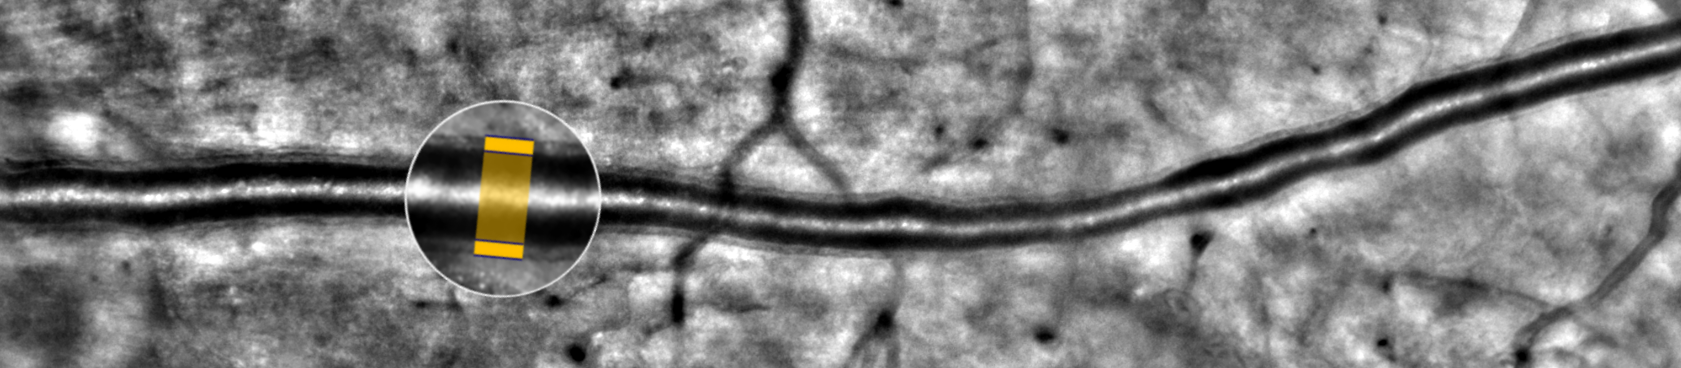

- novel microvascular assessments enabled by adaptive optics (AO) retinal imaging and flicker stimulation,

We are grateful to Dr. Céline Faure and Prof. Michel Paques for sharing their findings and methods from clinical research studies conducted 15-20 National Eye Hospital and Saint-Martin Private Hospital using rtx1 AO retinal cameras.